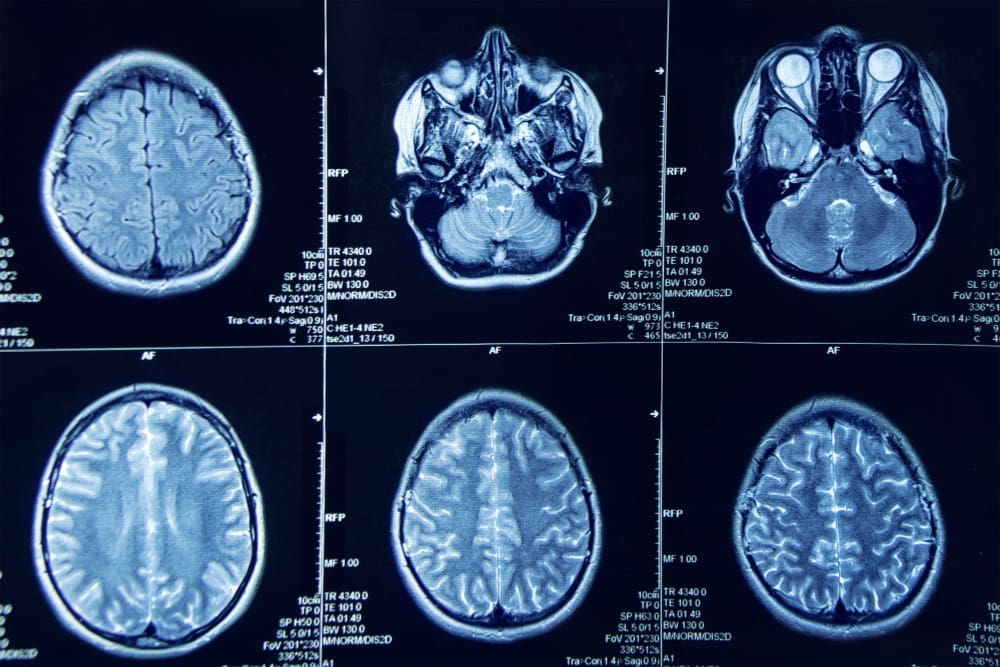

Meningiomas are tumors that grow from the meninges. These are protective membranes around the brain and spinal cord. Knowing their types and classifications is key to understanding treatment and prognosis.

Meningiomas are usually benign tumors from the meninges. They can grow at different rates. Many are found by chance during scans for other reasons.